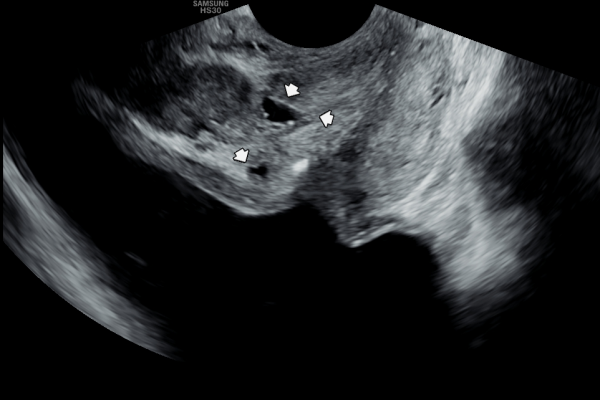

5년뒤 바쁜 일상 생활로 전립선의 관리를 하지 못하고 고환의 통증과 빈뇨 그리고 회음부 통증이 심해진다고 내원 당일 검사한 경직장 전립선 초음파 검사상 사정관 낭종과 낭종내 미세 결석이 생기고 사정관이 탈락된 상피 세포가 70%가량 좁아지고 전립선관도 순환 장애로 전립선 낭종이 관찰되는 초음파 사진입니다.

This transrectal prostate ultrasound image was taken on the day of the visit, five years later. Due to a busy lifestyle, the patient was unable to maintain prostate care and began experiencing worsening testicular pain, frequent urination, and perineal discomfort. The scan shows an ejaculatory duct cyst with microcalcifications inside, as well as narrowing of about 70% of the duct caused by accumulated epithelial cells. Circulatory issues have also led to the formation of prostatic cysts in the prostatic ducts.